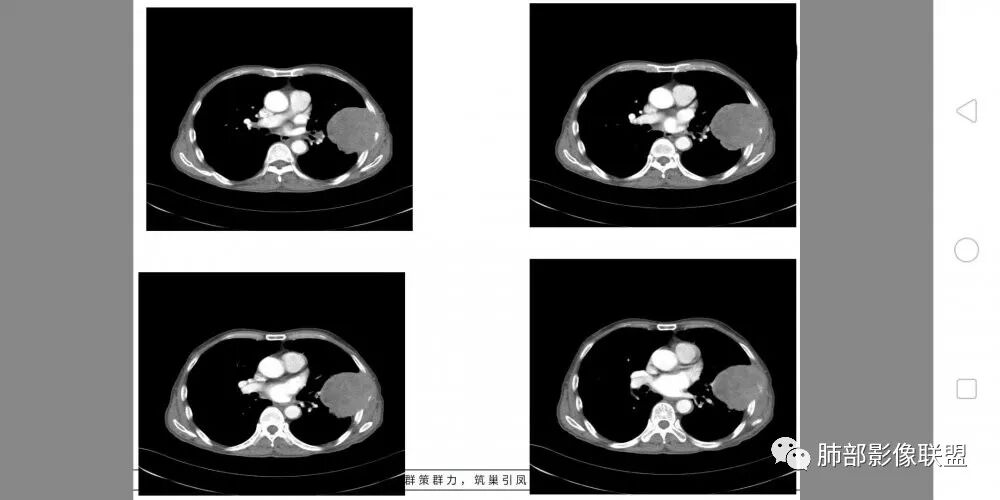

老年男性,外伤入院,“左上肺”实性肿块,边缘光滑,突破壁层胸膜并侵犯肋骨及肋间肌,增强扫描轻度强化,可见明显坏死。

左肺上叶实性肿物,左肺上叶支气管受压变窄,病灶边缘光滑,轻度分叶,病灶轻度强化内部可见多发小灶坏死,坏死边界模糊,病灶突破壁层胸膜侵及左侧部分肋骨及肋间肌,考虑恶性,肉瘤样癌,鉴别诊断低分化腺癌。

患者中老年男性,外伤后入院。胸部CT:左肺上叶实性肿块,近心侧边界清楚,边缘光滑,胸壁侧突破壁层胸膜、肋间隙并侵犯肋骨及肋间肌,增强扫描轻度强化,可见近心侧多发片状坏死,未见明显淋巴结肿大。综合考虑SFT,鉴别肉瘤及结核。

胸CT:左上肺实性大肿块,边缘光滑,突破胸膜侵犯肋骨及肋间肌,纵隔淋巴结肿大,增强呈轻度强化,可见明显片状坏死。

胸部CT所见左肺上叶尖后段胸膜下较大山丘形肿块,边界清楚,宽基底与胸膜相贴,边缘与胸膜呈直角及锐角相交。邻近上叶尖后段支气管受压推挤,叶裂局部膨隆,病灶周围见少许磨玻璃密度影,边界不清。纵膈窗显示,肿块密度均匀,增强扫描呈不均匀轻度强化,邻近肋骨骨质破坏,病变沿肋间隙向外侵犯,局部胸膜增厚。纵膈内见多发小淋巴结,未见胸腔积液征象。综合考虑恶性占位,肉瘤样癌可能性大。腰椎及髋部考虑骨转移。

老年男性,左肺上叶舌段胸膜下肿块,外朝内生长,对应支气管受压变窄,肿块边界清晰,邻近胸膜胸壁和肋骨受侵犯,增强扫描明显不均匀强化,内有较多坏死,考虑恶性,首先肉瘤样癌,鉴别低分化腺癌。